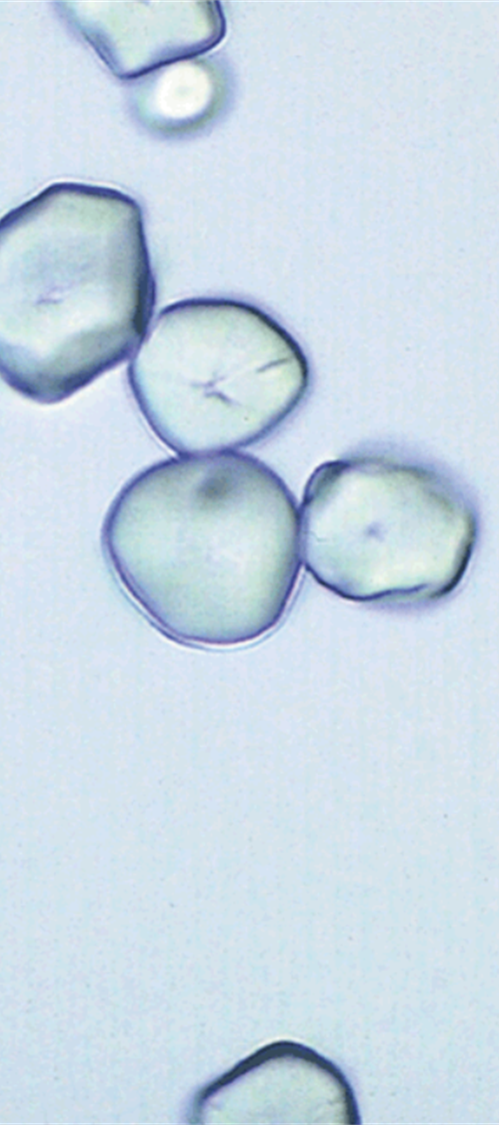

Calcium Oxalate

knowt flashcard image

In increased numbers it could indicate formation of renal calculi